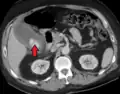

Acute cholecystitis with gallbladder wall thickening, a large gallstone, and a large gallbladder- Significant gallbladder wall thickening[29]

- Significant gallbladder wall thickening[29]